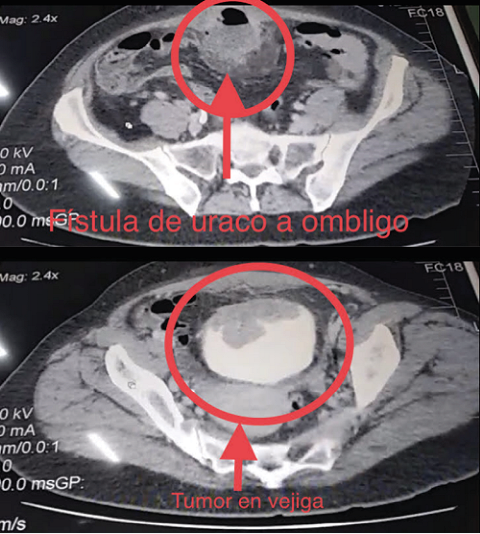

With cures and drains without improvement, later presenting difficulty in urination and copious mucosuria, the patient attended the clinic for treatment, Initially a contrasted thoraco-abdominal-pelvic tomography with elimination phase was performed (see image 2).

Documenting a tumor involving the roof of the bladder, anterior wall of the rectus abdominis muscle and fistulizing to the umbilicus, without lymph nodes or metastasis in other sites, A control cystoscopy was performed (see image 3).